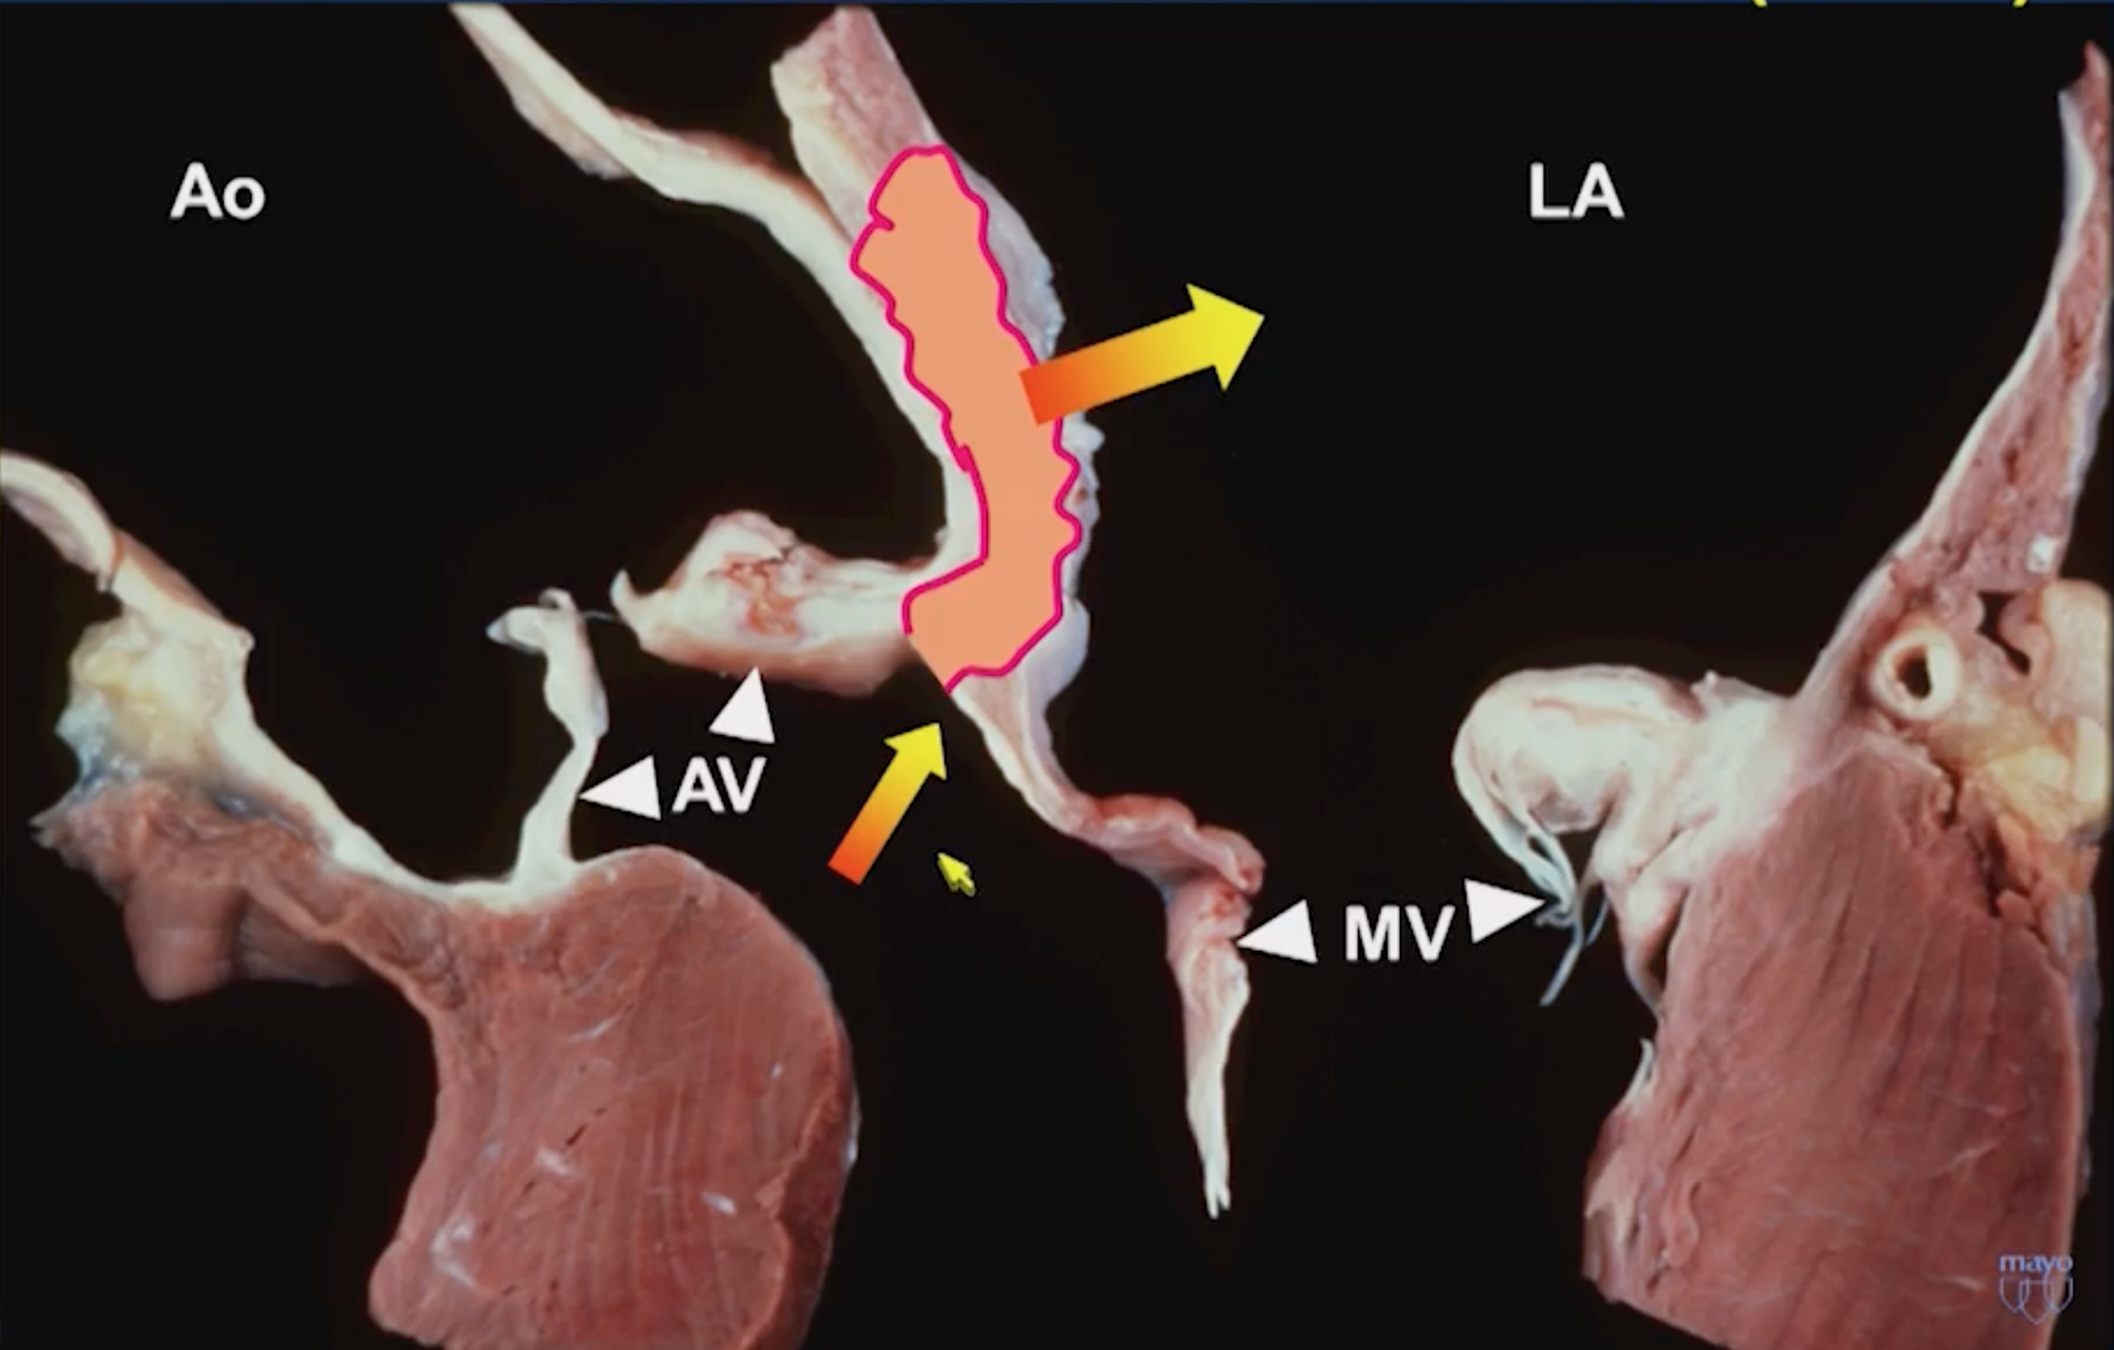

Mitral Aortic Intervalvular Fibrosa MAIF

Fibrous region of the heart that connects the anterior mitral leaflet to the posterior aortic root and communicates with the left ventricular outflow tract

MAIF Pseudoaneurysm